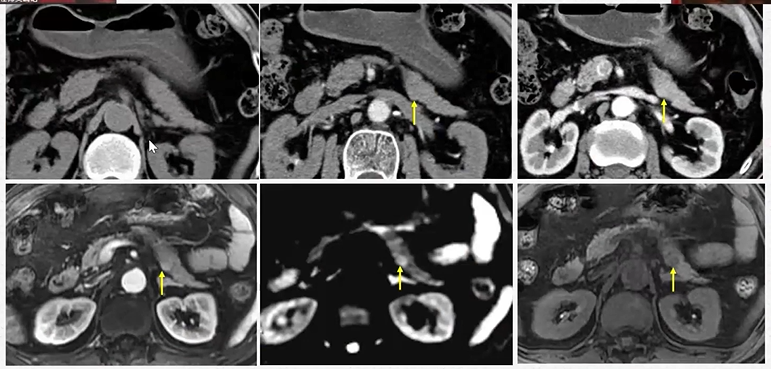

04

反复阅片:胰岛素瘤

图8 反复阅片:胰岛素瘤

(图片来源:余日胜教授讲课使用)